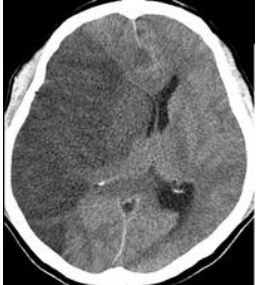

16 確定病灶後,王先生選擇接受開刀治療,術後恢復順利,但一週後開始出現嗜睡、意識不清,抽血 檢查鈉離子 136 mEq/L,電腦斷層檢查如下圖,王先生可能出現何種併發症?

(A)血管痙攣(vasospasm) (B)急性水腦症(acute hydrocephalus) (C)再出血(rebleeding) (D)低血鈉(hyponatremia)